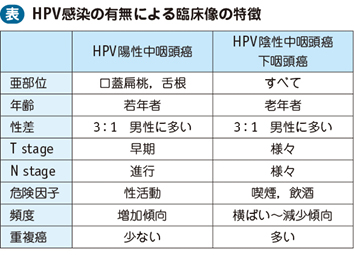

頭頸部癌 最近の診断 治療の進歩 耳鼻咽喉 頭頸科 順天堂医院